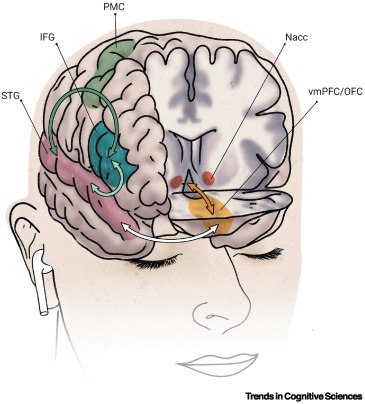

为什么有些人似乎天生就对音乐“无感”?近期一篇发表于《认知科学趋势》的综述文章,深入探讨了“特定音乐快感缺失症” (specific musical anhedonia) 。这类人群并非听力或音乐感知能力有障碍,也能从金钱等其他事物中获得正常的愉悦感,但唯独无法从音乐中感受到任何乐趣

研究指出,问题的核心不在于大脑的奖赏系统本身,而在于听觉系统与奖赏系统之间的“线路连接” 。神经影像学研究发现,这类人群在听音乐时,大脑中负责声音处理的右侧颞上回与奖赏中心伏隔核之间的功能性连接强度显著低于常人。这意味着,尽管音乐信息被大脑准确接收,但通往“快乐中枢”的通路受阻,无法有效触发愉悦体验。

该研究模型不仅为我们理解个体音乐偏好的差异提供了新视角,也暗示了其他特定类型的快感缺失(如社交、美食等)可能也源于类似的感知 - 奖赏“断联”机制 。这为未来研究成瘾、抑郁症等相关精神障碍提供了新的方向。